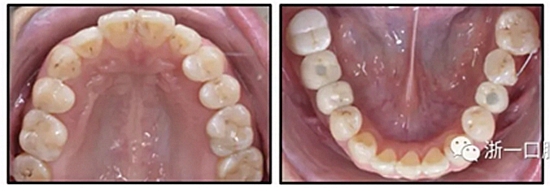

圖3. 治療后面部和口內(nèi)照片

圖4. 治療后研究模型